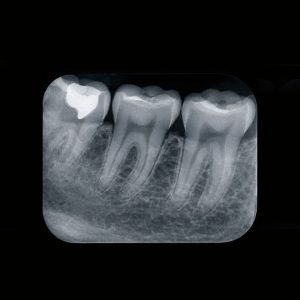

- Za otkrivanje skrivenih problema – karijes, ciste, zapaljenja

- U protetici i implantologiji za precizno planiranje rada